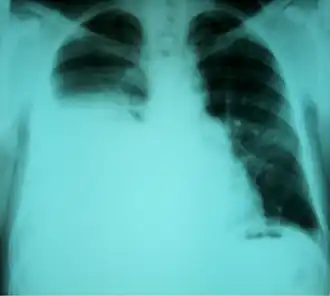

| Radiografia torácica mostrando um hidrotórax hepático em uma pessoa com cirrose | |